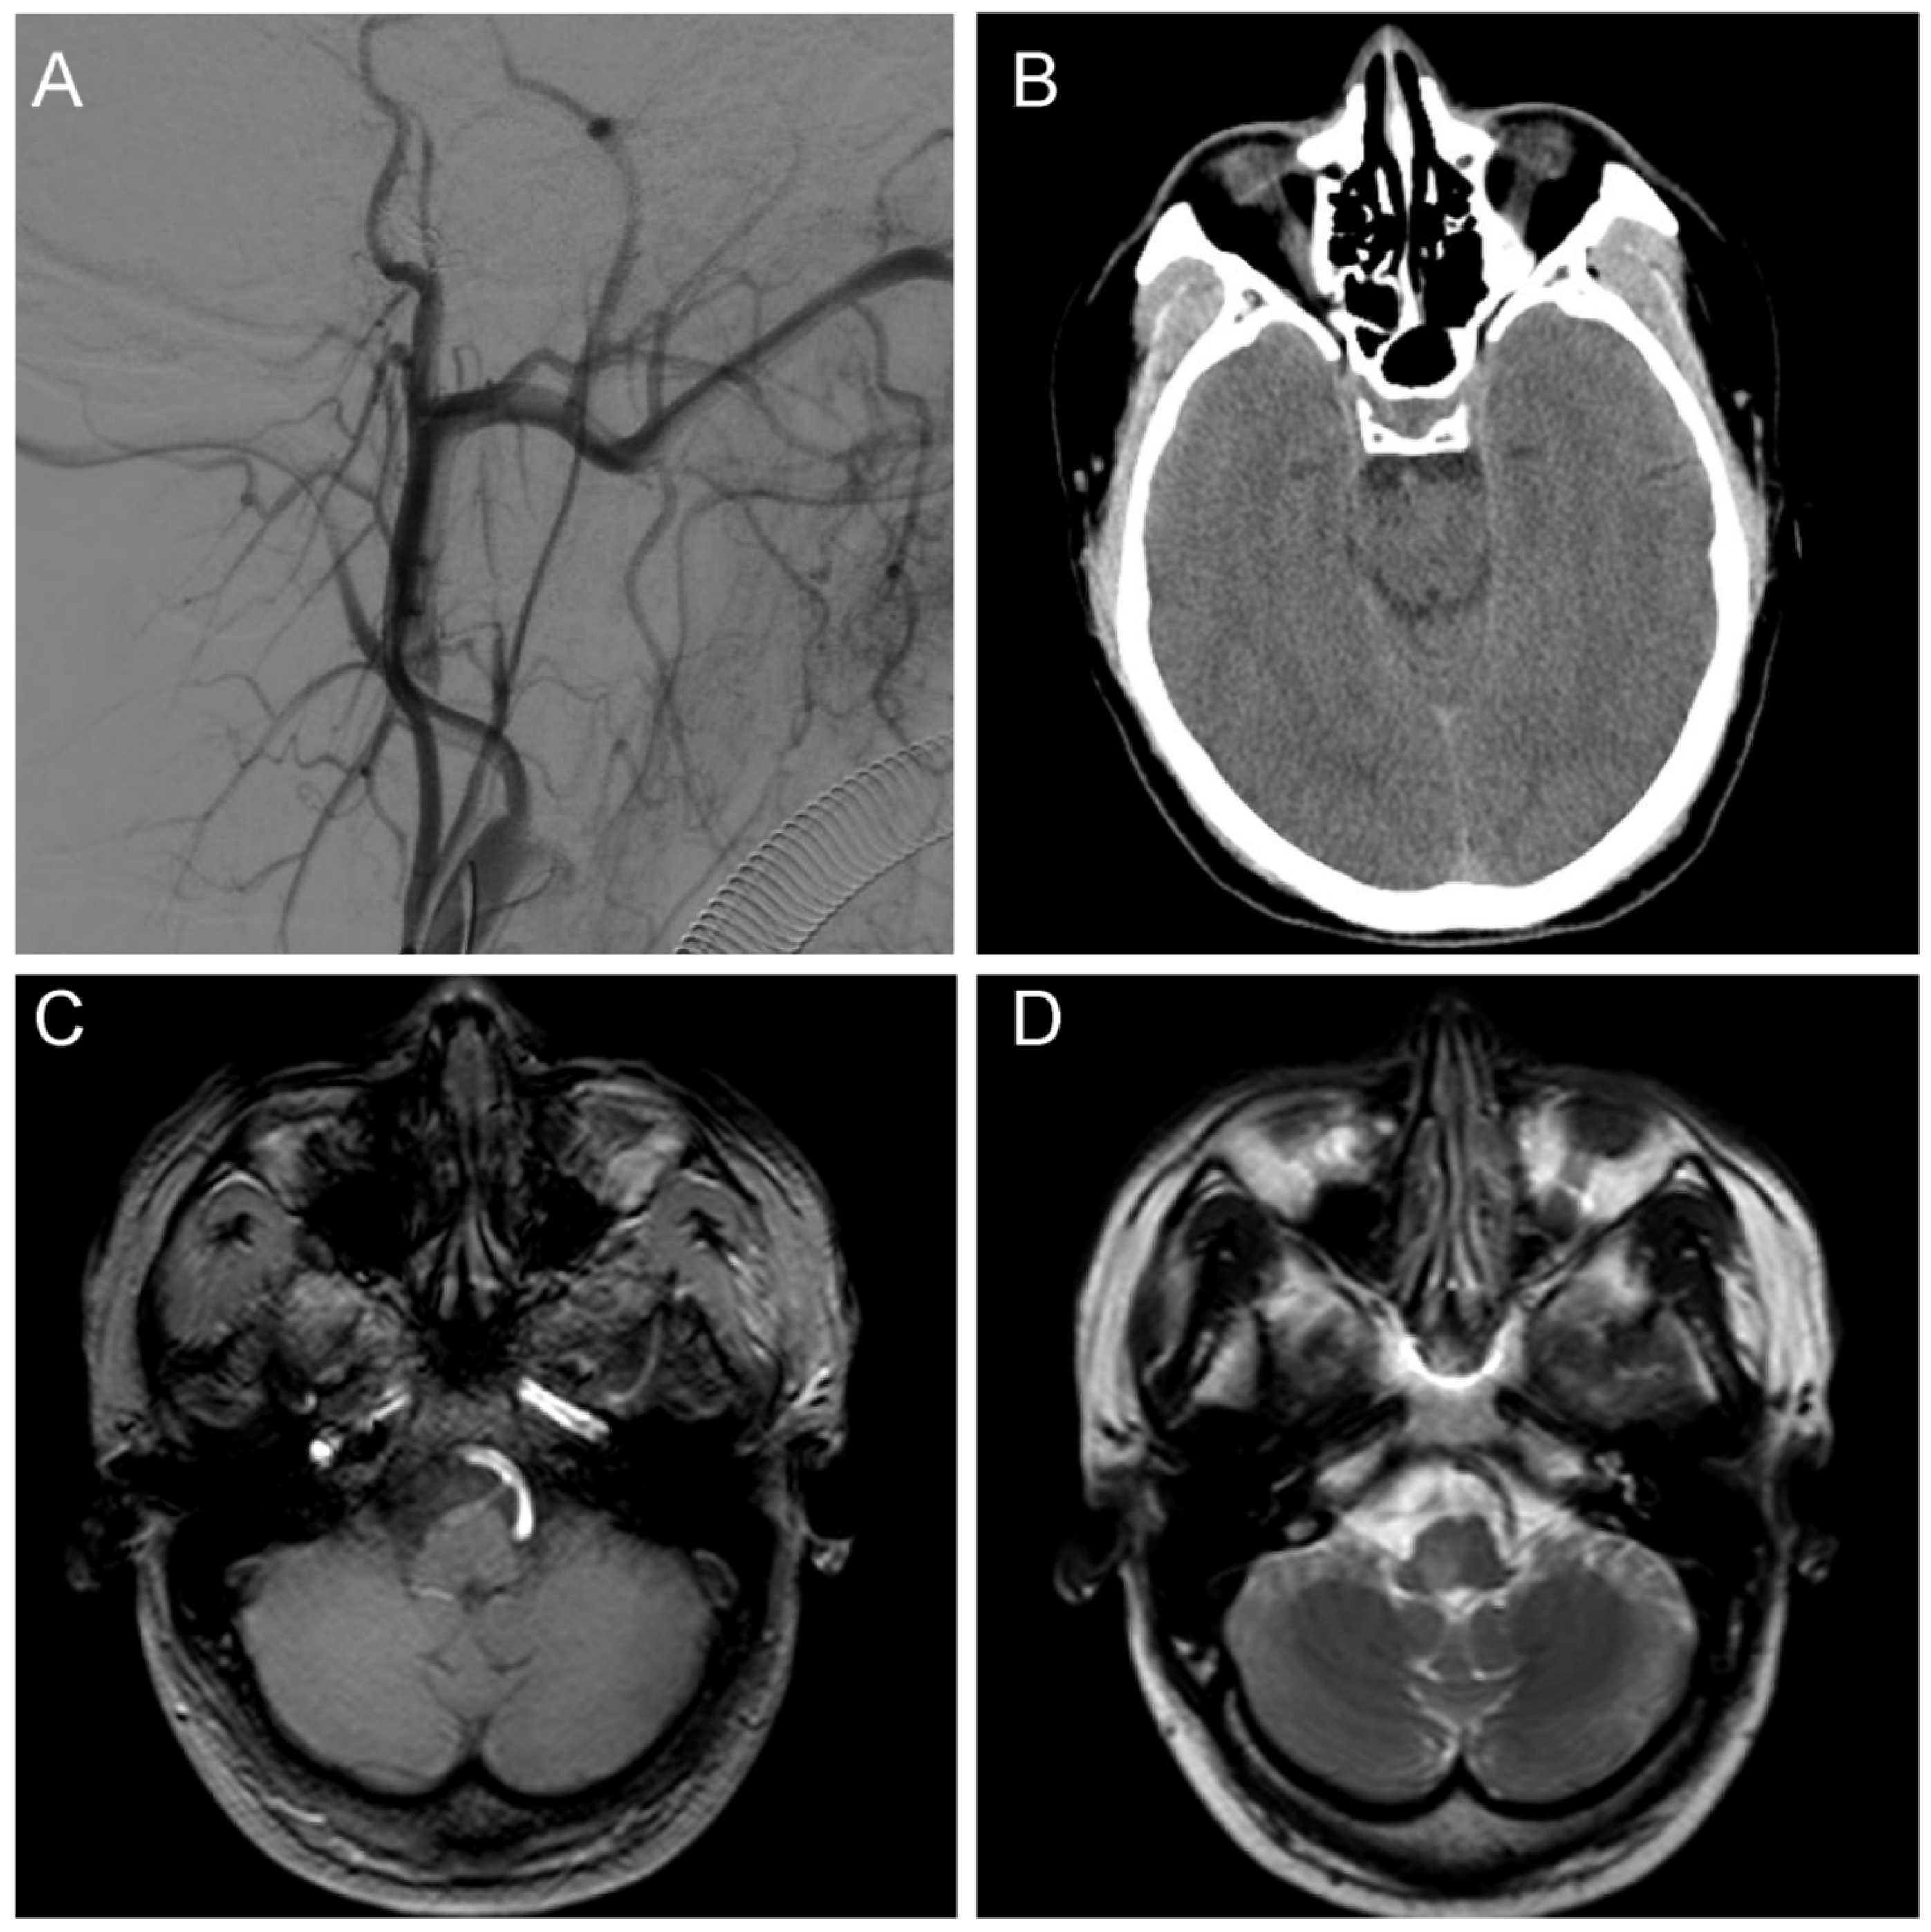

Figure 4.

Postoperative examination. (A) A postoperative DSA examination indicated complete fistula occlusion; (B) A CT examination indicated no hemorrhage and ischemia at the site of the lesion; (C) The T1 sequence of MRI showed a slightly long signal area in the brainstem without abnormal postoperative injuries; (D) The T2 sequence of MRI showed a slightly long signal area in the brainstem with a normal cranial structure.